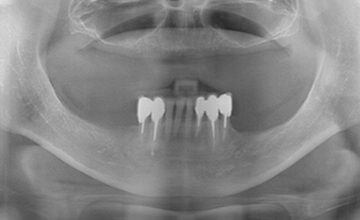

여러 개의 임플란트를 심은 뒤, 그 사이를 금속 막대로 연결해 튼튼한 지지대를

만들고, 그 위에 틀니를 안정적으로 고정하는 방식입니다.